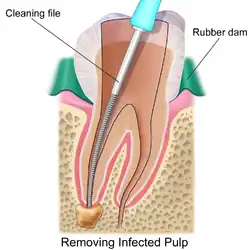

Isolating the tooth

The use of a rubber dam for tooth isolation is mandatory in endodontic treatment for several reasons:

- It provides an aseptic operating field, isolating the tooth from oral and salivary contamination. Root canal contamination with saliva introduces new microorganisms to the root canal which compromise the prognosis.

- It facilitates the use of the strong medicaments necessary to clean the root canal system.

- It protects the patient from the inhalation or ingestion of endodontic instruments.

Removal of pulp tissue

If a tooth is considered so threatened (because of decay, cracking, etc.) that future infection is considered very likely or inevitable, a pulpectomy (removal of the pulp tissue) is advisable to prevent such infection. Usually, some inflammation and/or infection is already present within and/or below the tooth. To cure the infection and save the tooth, the dentist drills into the pulp chamber and removes the infected pulp. To eliminate bacteria from the pulp chamber and root canals, the use of efficient antiseptics and disinfectants is necessary.[11] The soft tissues are either drilled out of the root canal(s) with engine driven rotary files, or with long needle-shaped hand instruments known as hand files (H files and K files).